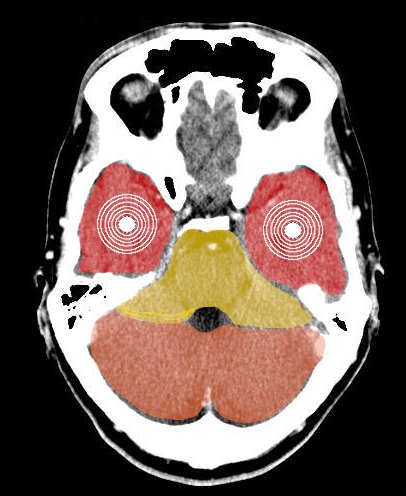

Secondo le 5LB le allucinazioni sono per lo più segnali di una costellazione della corteccia cerebrale, quindi ectodermica. In questa costellazione la percezione allucinatoria avviene in corso di conflitto attivo o di Crisi Epilettoide. A seconda dei relè coinvolti si possono avere:- allucinazioni olfattive quando sono interessati i relè corticali nasali posti nell'area sensoria della corteccia. La persona ha la sensazione di percepire odori particolari in realtà inesistenti

- allucinazioni visive, quando siano coinvolti entrambi i relè della retina posti nella corteccia visiva. La persona ha la netta sensazione di vedere qualcosa che in realtà non esiste

- allucinazioni uditive, quando siano coinvolti entrambi i relè uditivi posti nella corteccia sensoria uditiva. La persona può percepire suoni o più frequentemente delle voci.